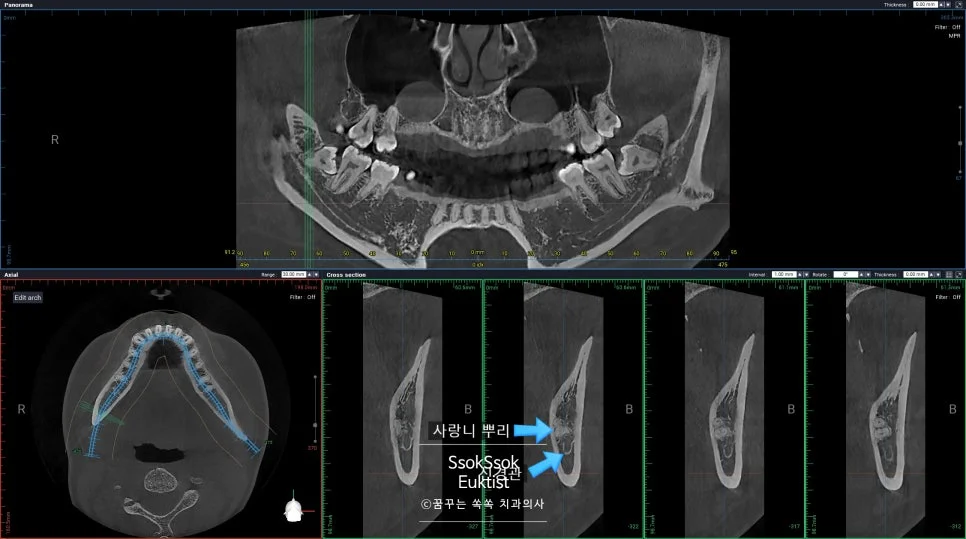

오른쪽 아래 사랑니의 경우 신경관과 바로 붙어 있습니다.

오른쪽 아래 사랑니 — 신경관과 바로 붙어 있는 상태

하지만 그보다 더 걱정인 건 사랑니 뿌리의 모양인데요.

사랑니 뿌리가 서로 다른 방향으로 휘어 있는 구조

뿌리가 서로 다른 방향으로 휘어 있어 한 번에 나올 수 없는 상황인데요. 이런 경우 뿌리가 전부 나오지 않고 뿌리의 조각이 일부 남아 있게 될 수 있습니다.

우선은 수면 마취 하에 제거를 시도해 봅니다!

역시나 아래쪽 뿌리 일부가 남게 된 상태